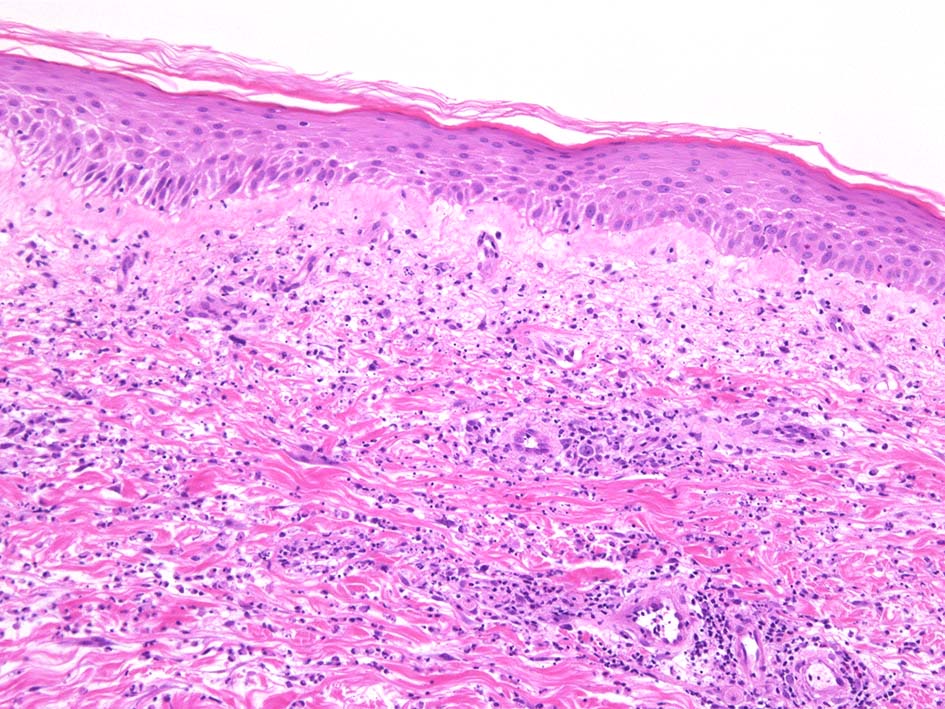

HE x40. Sweet病最盛期皮膚病変の所見があります.

表皮下水疱, 真皮上層の細血管周囲に密な好中球浸潤あり.(thumb nail clickで大きなphotoが見られます)

典型疹は真皮の好中球浸潤より始まる. 病初期では, 好中球浸潤は表皮に及ばない. 病期が進むにつれ, 2次的好中球浸潤が認められるようになる.

真皮上中層で広範囲に好中球が密に浸潤する所見がSweet病の最大の特徴. 好中球活性が亢進し, apoptosisを起こして核塵(核破砕物)がみられることが多い. 浸潤が顕著になると真皮上中層が浮腫をきたして, 皮疹が隆起する.

真皮上層浮腫がつよくなり表皮下水疱を形成することがある. 水疱内にはフィブリンや炎症細胞が多数認められる.

真皮の好中球浸潤部には毛細血管, 細動静脈が巻き込まれるが, 血管のフィブリノイド壊死は認められない.(鑑別が難しいことのあるBehçet病では2012年より, 壊死性血管炎があるとされており鑑別のための病理所見となっている)